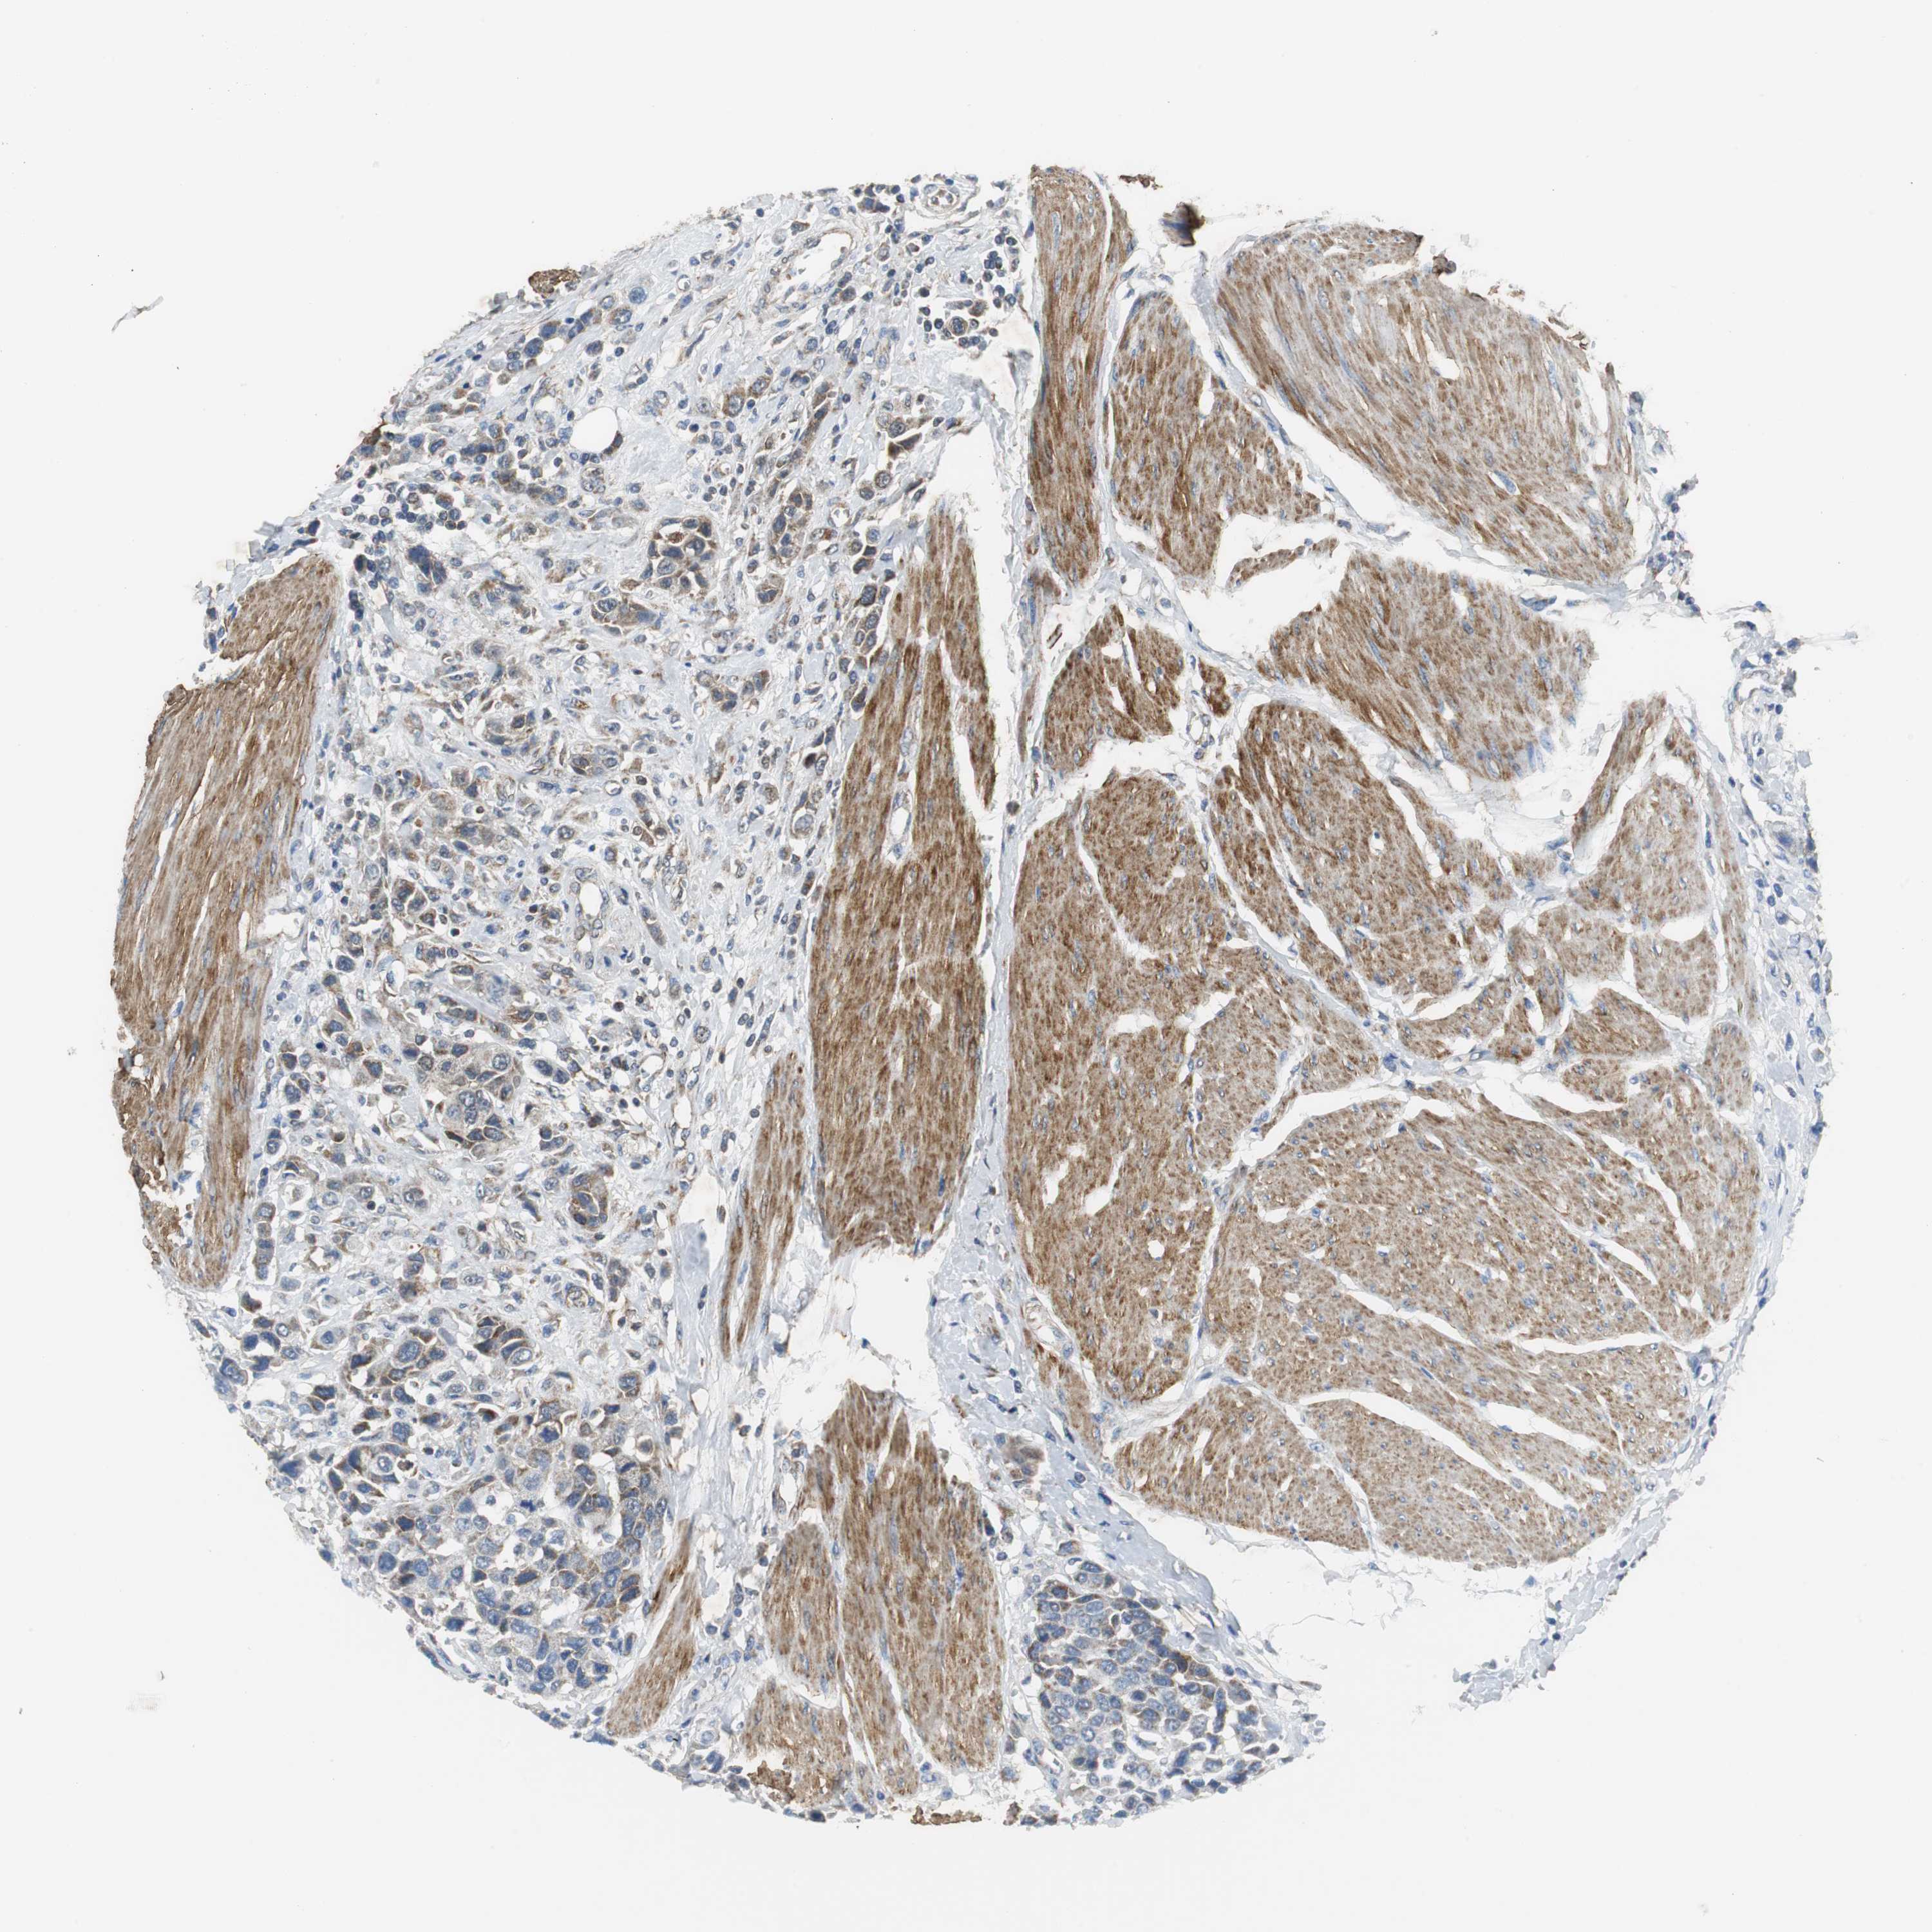

UROTHELIAL CANCER - Protein expressioni

A mouse-over function shows sample information and annotation data. Click on an image to view it in a full screen mode. Samples can be filtered based on level of antibody staining by selecting one or several of the following categories: high, medium, low and not detected. The assay and annotation is described here.

Antibody stainingi

Antibody staining in the annotated cell types in the current human tissue is reported as not detected, low, medium, or high, based on conventional immunohistochemistry profiling in selected tissues. This score is based on the combination of the staining intensity and fraction of stained cells.

Each image is clickable and will lead to virtual microscopy that enables deeper exploration of all samples and also displays staining intensity scores, fraction scores and subcellular localization as well as patient and tissue information for each sample.

Antibody HPA004829

Antibody CAB004975

Staining

High

Medium

Low

Not detected

Intensity

Strong

Moderate

Weak

Negative

Quantity

>75%

75%-25%

<25%

None

Location

Nuclear

Cytoplasmic/membranous

Cytoplasmic/membranous,nuclear

Urothelial carcinoma, High grade

Urothelial carcinoma, Low grade